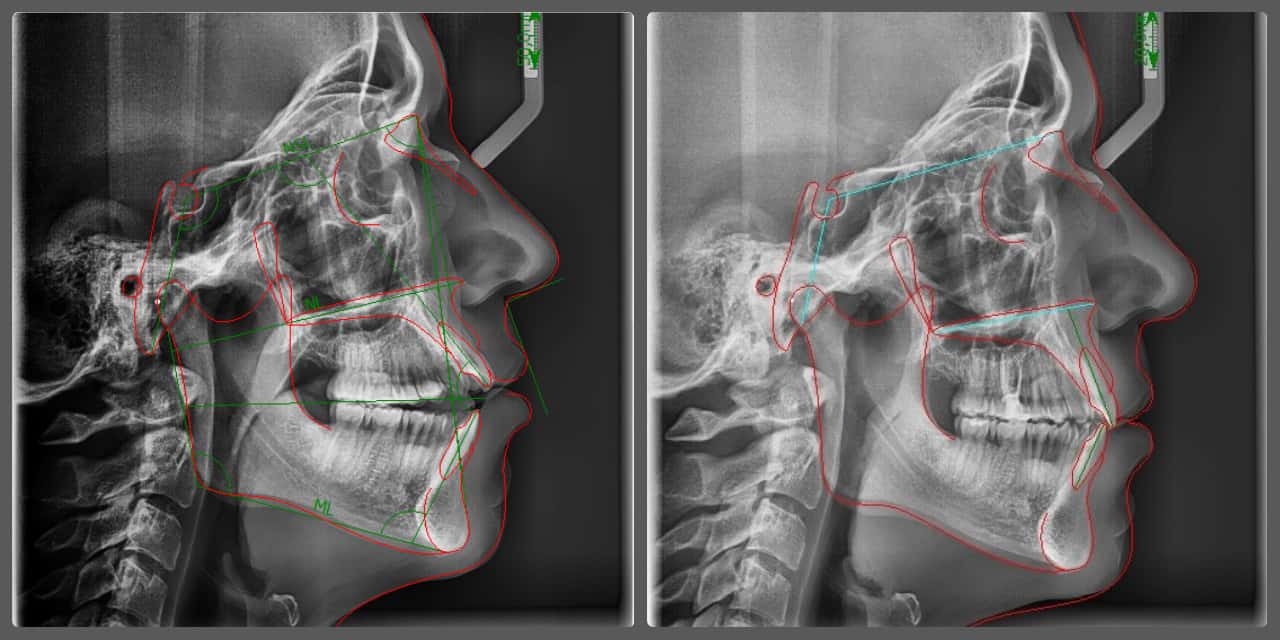

Balázs súlyos alsó torlódása miatt keresett fel magánrendelésemen. A diagnosztikus vizsgálatok során előbbin túl alsó-felső fogívszűkületet, valamint nyitott harapási hajlamot állapítottam meg. Kezelését Pitts21 alsó-felső rögzített fogszabályozó készülékkel kezdtük meg. A nyitott harapási hajlamot a hátsó fogakra helyezett harapásemelővel kontrolláltuk. A torlódott fogaknak tolórugóval és interproximális redukcióval teremtettünk helyet, és intermaxilláris gumihúzással tökéletesítettük a harapást. A fogszabályzó kezelés teljes időtartama alatt Balázs 110%-osan együttműködő volt, ezért 21 hónap alatt sikerült kiemelkedő végeredményt elérnünk.